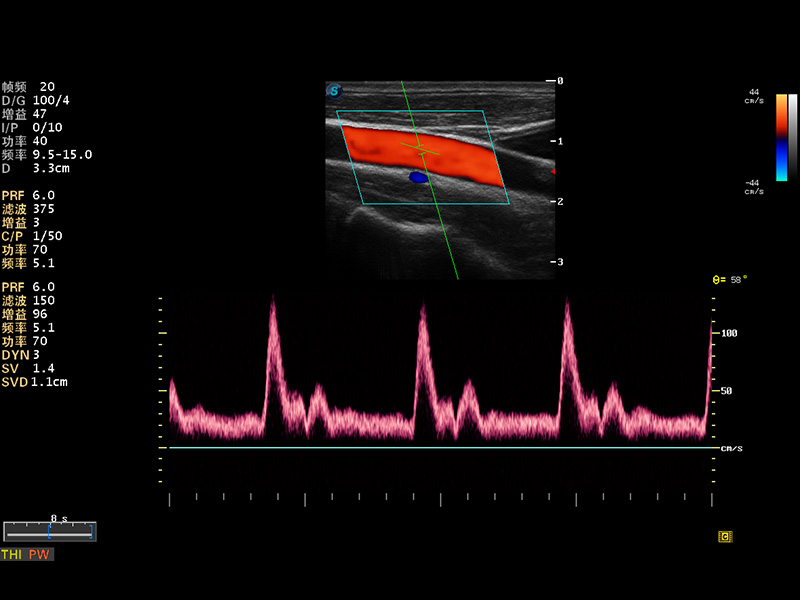

S8 EXP便携式彩色多普勒超声诊断仪是球速体育入口研发的高端全身应用型便携彩超。高通道的VIS平台融合可视化(Visual)、智能化(Intelligent)和人性化(Smart)的特点,配以球速体育入口自主研发生产的探头大家族,使您能够快速、准确的获得病人信息,提高工作效率的同时减轻疲劳。

成像技术

多波束形成器

μ-Scan微米成像

谐波成像

实时宽景成像

空间复合成像

3D/4D成像